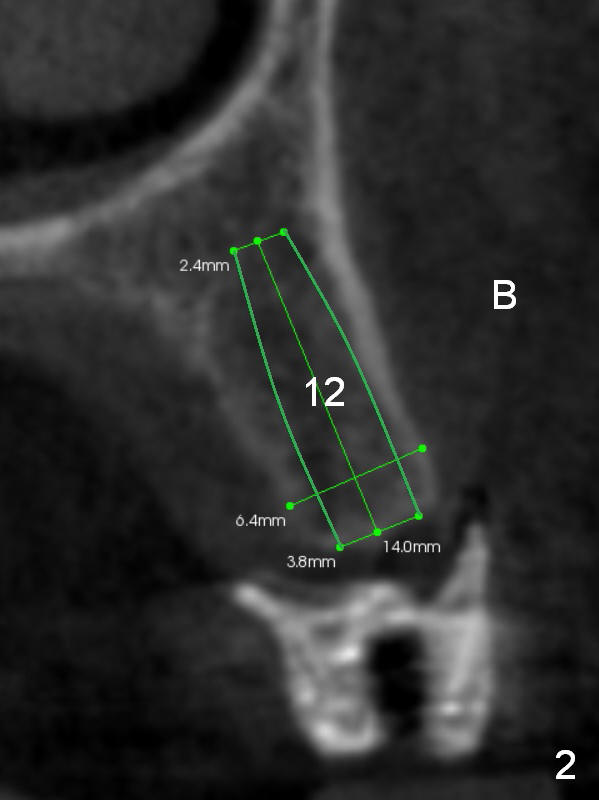

Three implants will be placed in the upper left posterior sextant (Fig.1-4). Without incision, place a surgical stent with trajectory tubes in place. Start osteotomy through the metal tubes (Fig.5,6) with a 2 mm pilot drill (SM) with drill extension if necessary. Palpate the buccal plate while drilling. Insert parallel pins for PA. According to the size of keratinized gingival band in the edentulous area, use either a 4 mm tissue punch or #15 scalpel for access. This way favors the trajectory over the diameter and length of the implants.